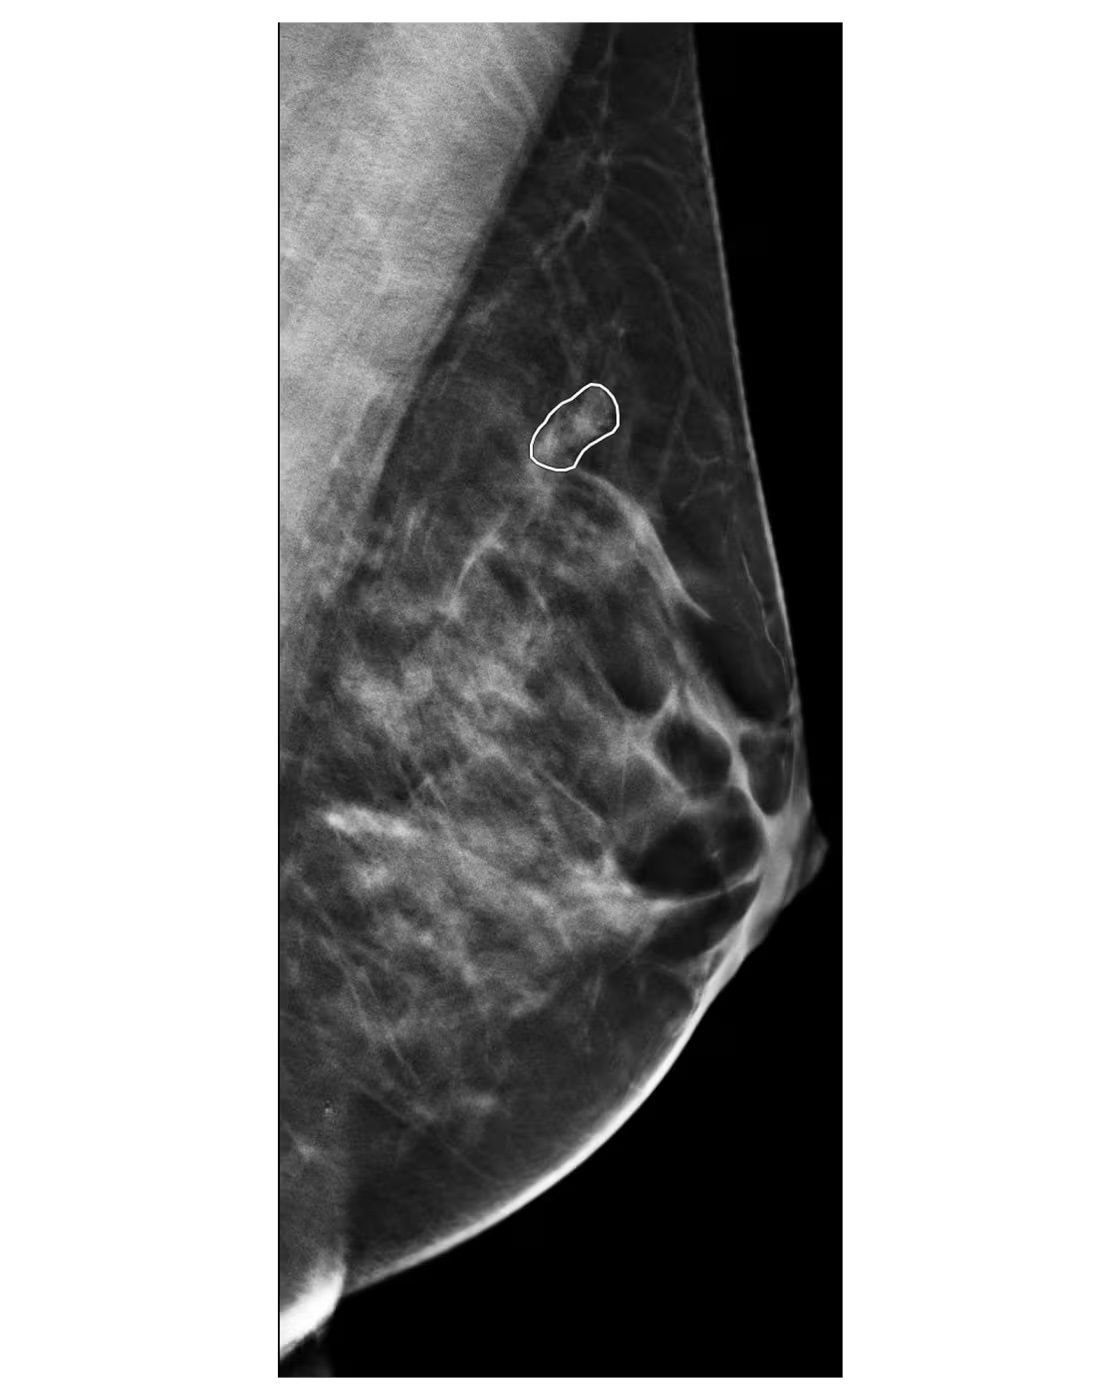

When AI flagged a subtle anomaly on Deirdre Hallโs mammogram โ a spot the radiologist initially missed โ it led to a biopsy that found four cancerous tumors.

Stage 1. No lymph node spread.

A near-miss that AI caught.

image: NBC News

Across the U.S., institutions like UCSF and Mount Sinai are using AI to triage mammograms faster and detect what human eyes might miss, especially in women with dense breast tissue. In one UCSF study, AI cut the time from scan to diagnosis from 73 days to just 9.